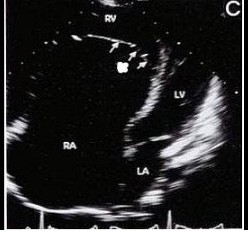

查看答案如图三尖瓣病例最可能的诊断

A、右室双腔

B、三尖瓣缺如

C、异位腱索

D、三尖瓣下移

E、室间隔缺损

查看答案